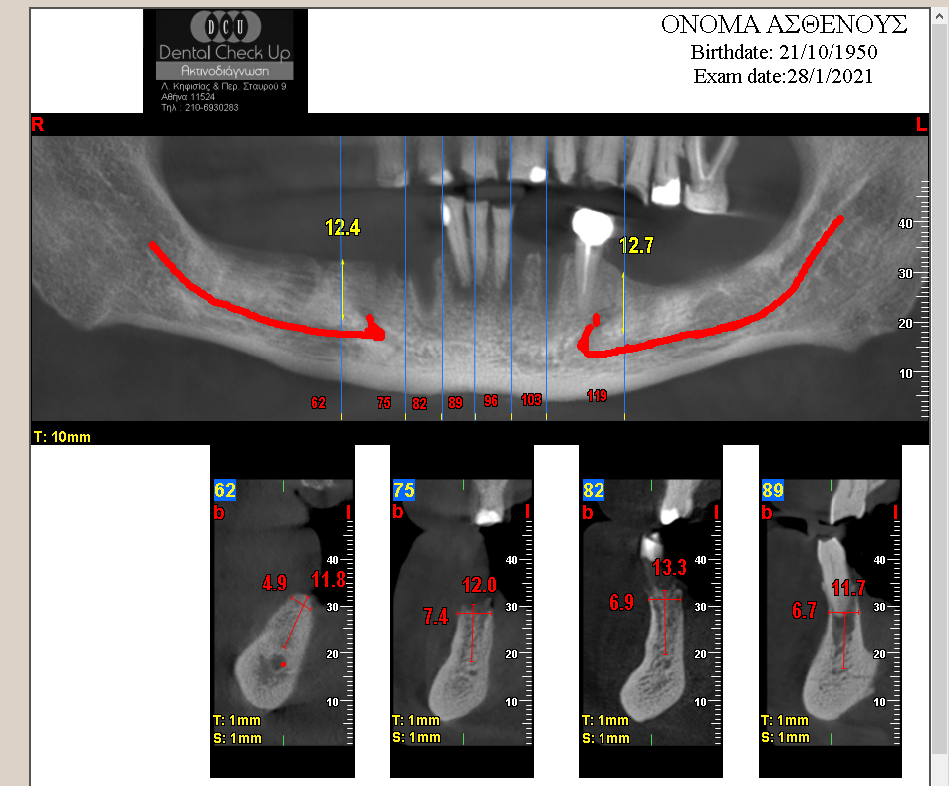

Επιλέγοντας report

Εμφανίζεται στην οθόνη η πρώτη σελίδα προς εκτύπωση. Με τα βέλη στον κόκκινο κύκλο στην εικόνα μετακινούμαστε στην επόμενη/επόμενες σελίδες. Με τα εργαλεία στον μπλε κύκλο μπορούμε να κάνουμε Zoom.

Έχουμε τις κάτωθι δυνατότητες :

- Αλλαγή φωτεινότητας (πατώντας δεξί click σε οποιαδήποτε εικόνα και επιλέγοντας change palette).

- Σβήσιμο προυπάρχουσας μέτρησης ή πραγματοποίηση νέας μέτρησης (δεξί click σε οποιαδήποτε κάθετη τομή και επιλέγοντας distances)

- Λεπτομερή απεικόνιση των τομών στην Panorex με δεξί click στις κάθετες τομές και επιλέγοντας Highlight crosses on Panorex.